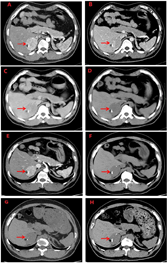

注:2021年4月1日双侧肾上腺磁共振平扫+增强:A:T1WI同相位;B:T1WI反相位;C:T2WI;D:T2WI SPIR;E:DWI b=0;F:DWI b=800;G:T1WI;H:增强动脉期;I:增强静脉期;J:增强延迟期。右侧肾上腺占位(如箭头所示)

醋酸氢化可的松起始剂量60 mg/d,根据病情调整剂量。2012年12月26日复查肾上腺CT平扫+增强(图2 E-F)示右侧肾上腺占位性变(5.6 cm×4.0 cm×4.1 cm)体积较未治疗前缩小约33%。2012年12月26日盆腔CT示:盆腔内可见子宫及附件结构,子宫大小、形态及密度未见异常。左侧附件见一大小约1.8 cm×1.4 cm囊性肿块,增强时囊壁强化。2013年5月份自觉双侧乳房增大、胀痛,自行将醋酸氢化可的松减量至40 mg/d后自觉乳房无继续增大,且胀痛减轻。根据患者治疗后复查的结果表明该患者原右侧肾上腺占位可能为皮质过度增生的结果,且患者强烈要求保留其男性社会性别,遵从患者意愿,醋酸氢化可的松减量为40 mg/d。2015年1月患者自行将醋酸氢化可的松减量至20 mg/d,2015年8月19日复查肾上腺CT示右侧肾上腺占位性病变与前比较未见明显变化(图2 G),建议予醋酸氢化可的松15 mg/d,但其自行减量至10 mg/d。2018年4月20日复查肾上腺CT示:右侧肾上腺占位性病变与前比较仍无明显变化(图2 H)。2021年4月1日双侧肾上腺MRI平扫+增强示:右侧肾上腺去见一稍短T1长T2信号灶,信号欠均匀,DWI呈高信号,其内见斑片状短T1长T2脂肪信号灶,压脂序列呈低信号,增强扫描明显不均匀强化区,其内脂肪成分未见强化,周围见斑片状延迟强化区,大小约5.0 cm×3.9 cm×4.9 cm;左侧肾上腺较同侧膈肌厚,最厚处约0.9 cm。双侧肾上腺与周围结构分界清楚。双侧肾上腺水平腹膜后淋巴结未见重度。提示右侧肾上腺占位较2018年4月缩小约4%,较未治疗前缩小约30%(图3)。阴囊、睾丸、阴阜超声提示:会阴部探及可显示腹腔内未见正常睾丸及附睾组织回声。治疗前后各项指标变化(图1)。